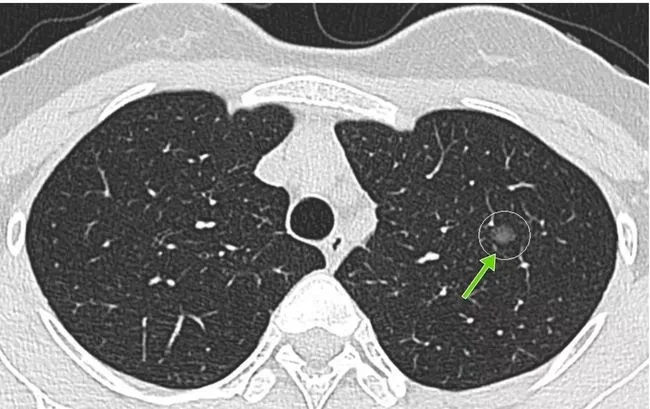

所謂的肺結(jié)節(jié),就是做胸部CT檢查時(shí)發(fā)現(xiàn)的肺部里密度增高的結(jié)節(jié)。

肺結(jié)節(jié)不是某種固定疾病的診斷,而是一個(gè)影像學(xué)上的定義。主要是指影像學(xué)表現(xiàn)為直徑≤3厘米的局灶性類圓形、密度增高的肺部陰影[1]。